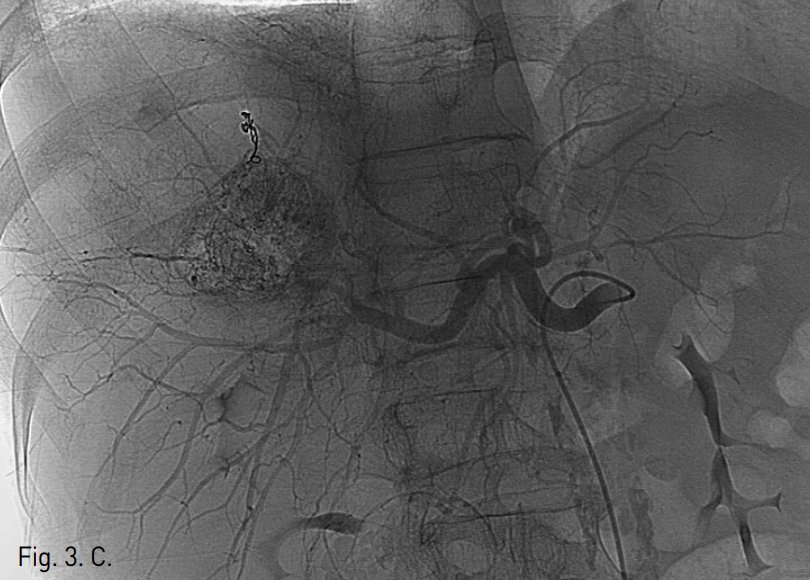

초음파 유도 하에 우측 대퇴동맥을 천자하여 5F vascular sheath를 삽입함. 5F RH catheter (Cook, Bloomington, USA)로 복강동맥을 선택한 후 시행한 동맥조영술에서 우간동맥 S7을 담당하는 분지동맥에서 기원하는 4cm 크기의 가성 동맥류가 관찰되었다(Fig. 3A). 먼저 RH catheter 내부에 2.2F microcatheter (Progreat, Terumo, Tokyo, Japan)를 삽입하여 가성 동맥류가 기원하는 혈관을 초선택하여 4개의 미세코일 (3mm x 2cm, Tornado embolization microcoil: Cook, Bloomington, IN, USA)을 이용해 색전하였다. 색전 후 시행한 동맥조영술에서 가성동맥류는 더 이상 조영되지 않았다. Coil 색전술 후 동맥조영술에서 인접하여 같은 분지동맥의 좀 더 근위부 동맥에 의해 공급받는 4.2cm 크기의 간세포암종으로 생각되는 비정상적인 과혈관성 병변이 좀 더 뚜렷하게 관찰되었다(Fig. 3B). 이후 과혈관성 병변을 공급하는 우간동맥의 분지동맥을 미세카테터로 초선택하여 항암제(Adriamycin 50mg)와 색전물질(Lipiodol 10cc)의 혼합물을 이용하여 화학색전술을 시행하였다. 화학색전 후 시행한 동맥조영술에서 종양이 조영되지 않고 내부가 lipiodol로 침착된 것 확인 후 시술을 종료하였다(Fig. 3C).

Fig. 3

C. Fluoroscopic image after coil and chemoembolization shows dense lipiodol uptake in the right postero-superior lobe of the liver.